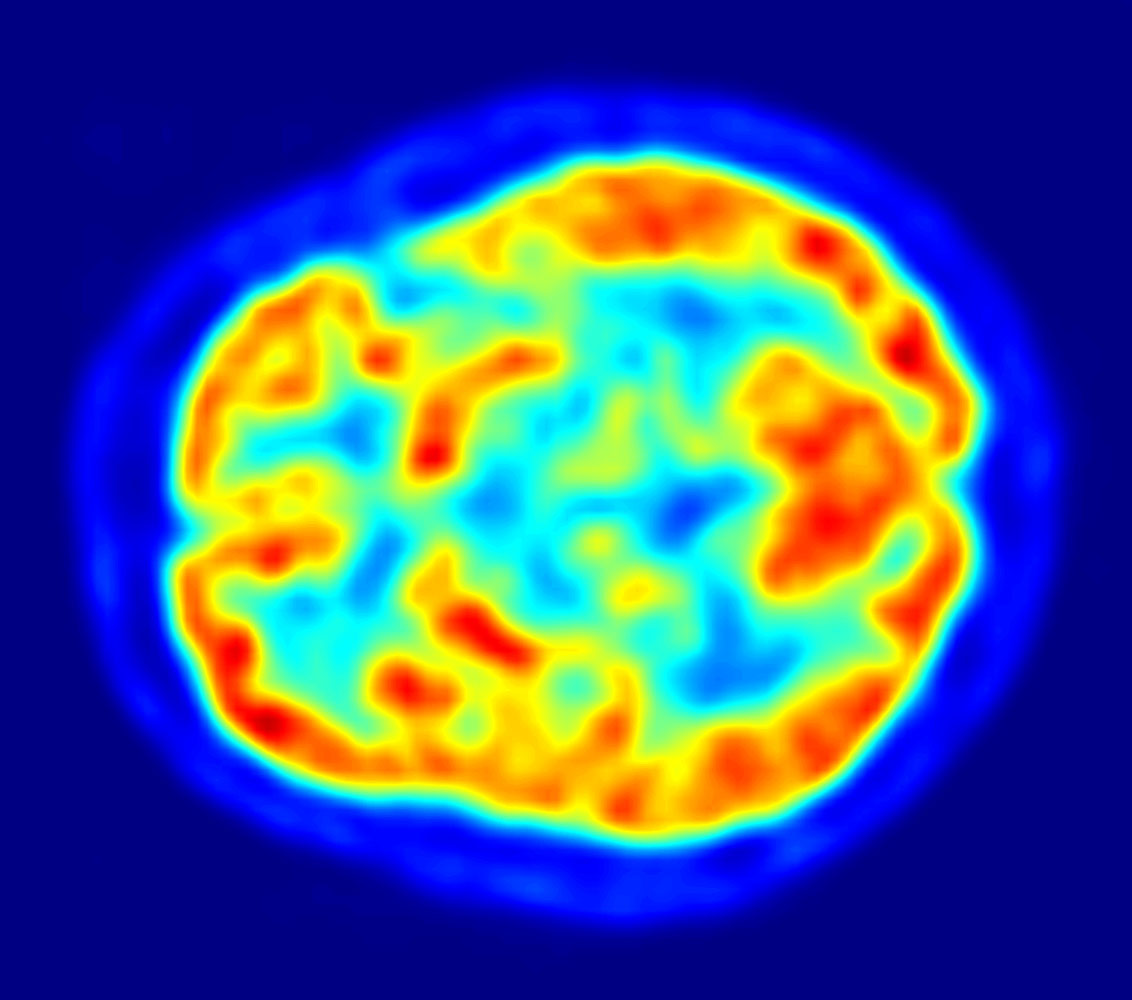

Brain FDG-PET phantom showing cortical glucose metabolism pattern, useful for Alzheimer's disease and epilepsy evaluation